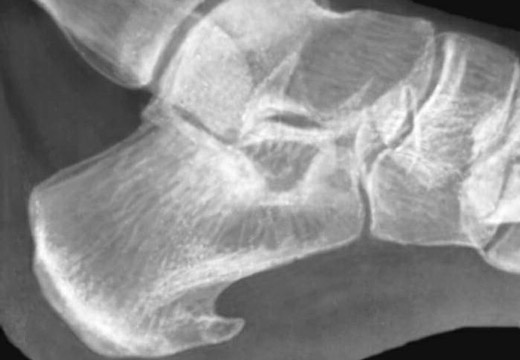

Лечение пяточной шпоры УВТ происходит в специализированном физиотерапевтическом кабинете медицинского учреждения в амбулаторных условиях. Перед назначением процедуры пациента осматривает ортопед и для подтверждения диагноза направляет больного на рентген и сдачу анализов. В отдельных случаях может понадобиться УЗИ, МРТ и коагулограмма.